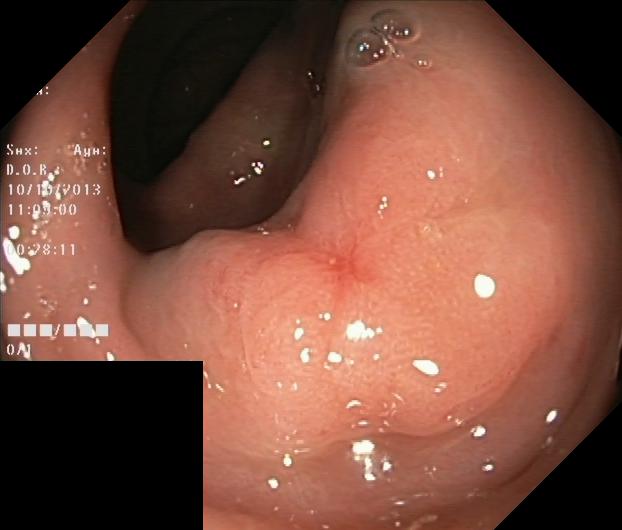

The Kvaris-SEG (Jha et al., 2020c) training dataset can be downloaded from https://datasets.simula.no/kvasir-seg/. It contains 1,000 polyp images and their corresponding ground truth mask as shown in Figure 1. The dataset was collected from real routine clinical examinations at Bærum Hospital in Norway by expert gastroenterologists. The resolution of images varies from to pixels. Some of the images contain a green thumbnail in the lower-left corner of the images showing the scope position marking from the ScopeGuide (Olympus) (see Figure 2). We annotate another separate dataset consisting of 160 new polyp images and use the resulting dataset as the test set to benchmark the participants’ approaches. Figure 2 shows some examples of test images used in the challenge.